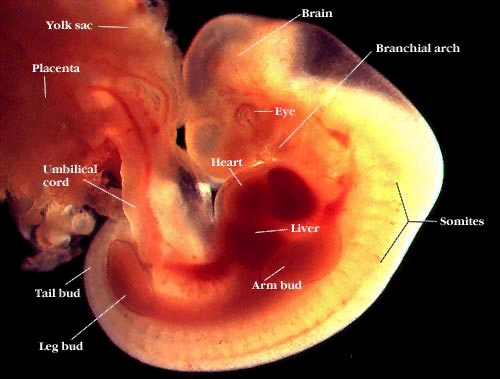

- Stærð fóstursins er nú u.þ.b. 4 mm og útlit þess minnir helst á sæhest. Fósturvísirinn stækkar fjörutíufalt fyrsta mánuðinn, hvorki meira né minna.

- Fósturvísirinn skiptist í þrjú lög.

- Miðtaugakerfið þróast út frá efsta laginu. Heilinn, mænan, mænutaugarnar og hryggsúlan myndast á þessu svæði. Fyrstu drög að augum og eyrum eru lögð.

- Hjartað og blóðrásarkerfið þróast út frá miðlaginu. Fyrstu blóðfrumurnar og blóðæðar myndast og pípulaga hjarta verður til. Fóstrið hefur þó ekki ennþá sína eigin blóðrás

- Vísir myndast að útlimum þ.e. höndum og fótum.

- Fygjan með fjölda háræða tengir fósturvísirinn við legvegginn.